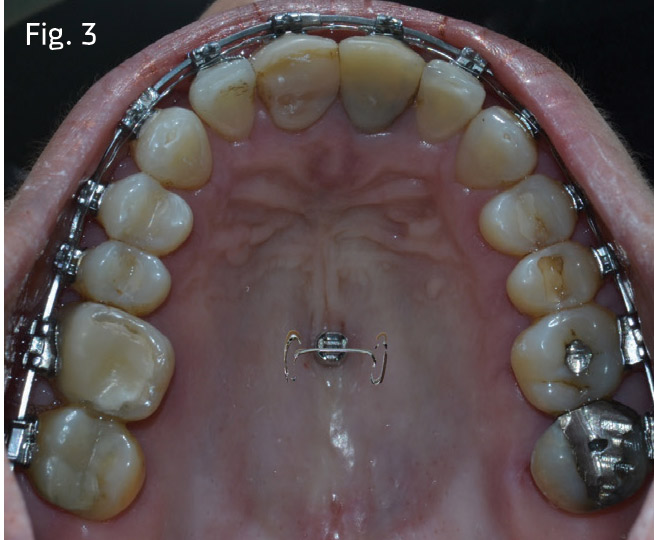

3. Create a simple way to apply, and then reapply, intrusive forces to the upper molars and second premolars. A dumbbell attachment (Figs. 2 and 3) can be bent from 19x25 stainless steel and bonded into the cross slot of any miniscrew with a slot in its head. It's a good idea to microetch the internal walls of the slot and apply a metal primer before bonding. A filled flowable restorative-grade composite is a good choice for this application, and the clinician should be careful to flow the material into the undercuts of the head of the miniscrew. Every 4 to 6 weeks, 75 grams of powerchain force can then be applied individually to the first and second molars, as well as the second premolars if they are included.

In both cases, passive self-ligating brackets with standard anterior torque prescription were placed. Quarter-inch, 2-ounce posterior cross-elastics were used as needed from the lingual of the upper molars to the labial of the lower molars from the first archwire insertion of .014 copper nickel titanium (CuNiTi). The archwire sequence of 14x25 unit, 18x25 CuNiTi, 19x25 stainless steel was followed with 10-week appointment intervals. The posterior crossbite relationships in Case 1 were corrected before advancement to 18x25 CuNiTi. In Case 1, once both arches were worked to 19x25 stainless steel, a Rocky Mountain Orthodontics fixed/removable transpalatal arch was inserted into the vertical lingual sheaths of the upper molar bands, with 6mm of clearance relative to the palate (Fig. 12). In Case 2, molar bands were avoided by placing a bonded TPA bent from .036 stainless steel. It was bonded to the occlusal surfaces of the upper first molars (see Fig. 13). This prevents lingual rolling of the buccal segments during intrusion.

In Case 1, a 6mm miniscrew was inserted at the midpalatal raphe at the mesial aspects of the first molars. A dumbbell attachment was bent from 19x25 stainless steel and bonded into the cross-slot of the miniscrew with filled flowable composite (Wave, Patterson Dental), and with composite carefully flowed into the undercuts of the head of the miniscrew.